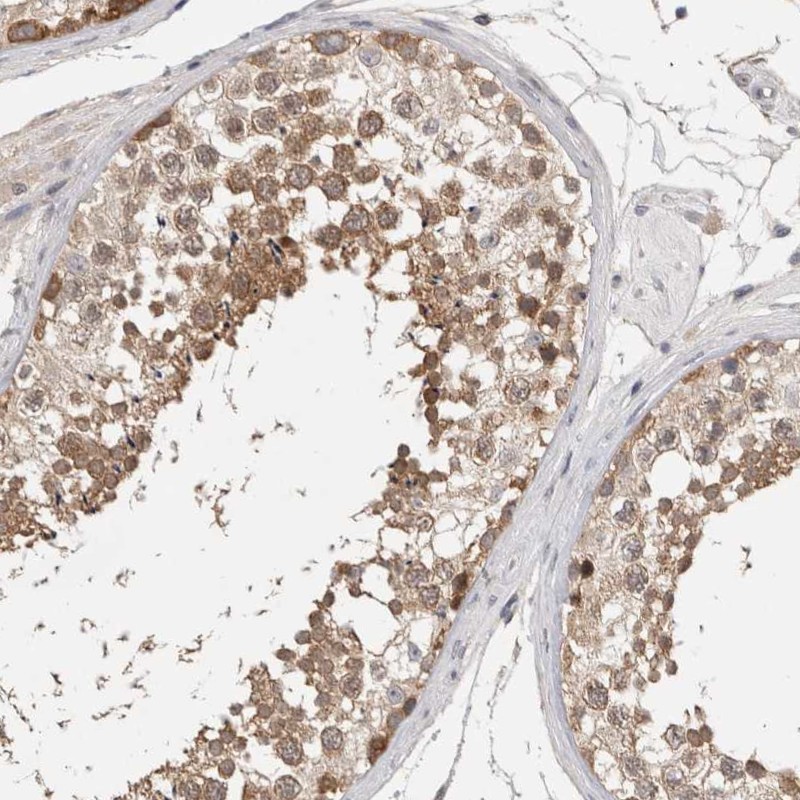

Immunohistochemical staining of human testis shows moderate cytoplasmic positivity in cells in seminiferous ducts.